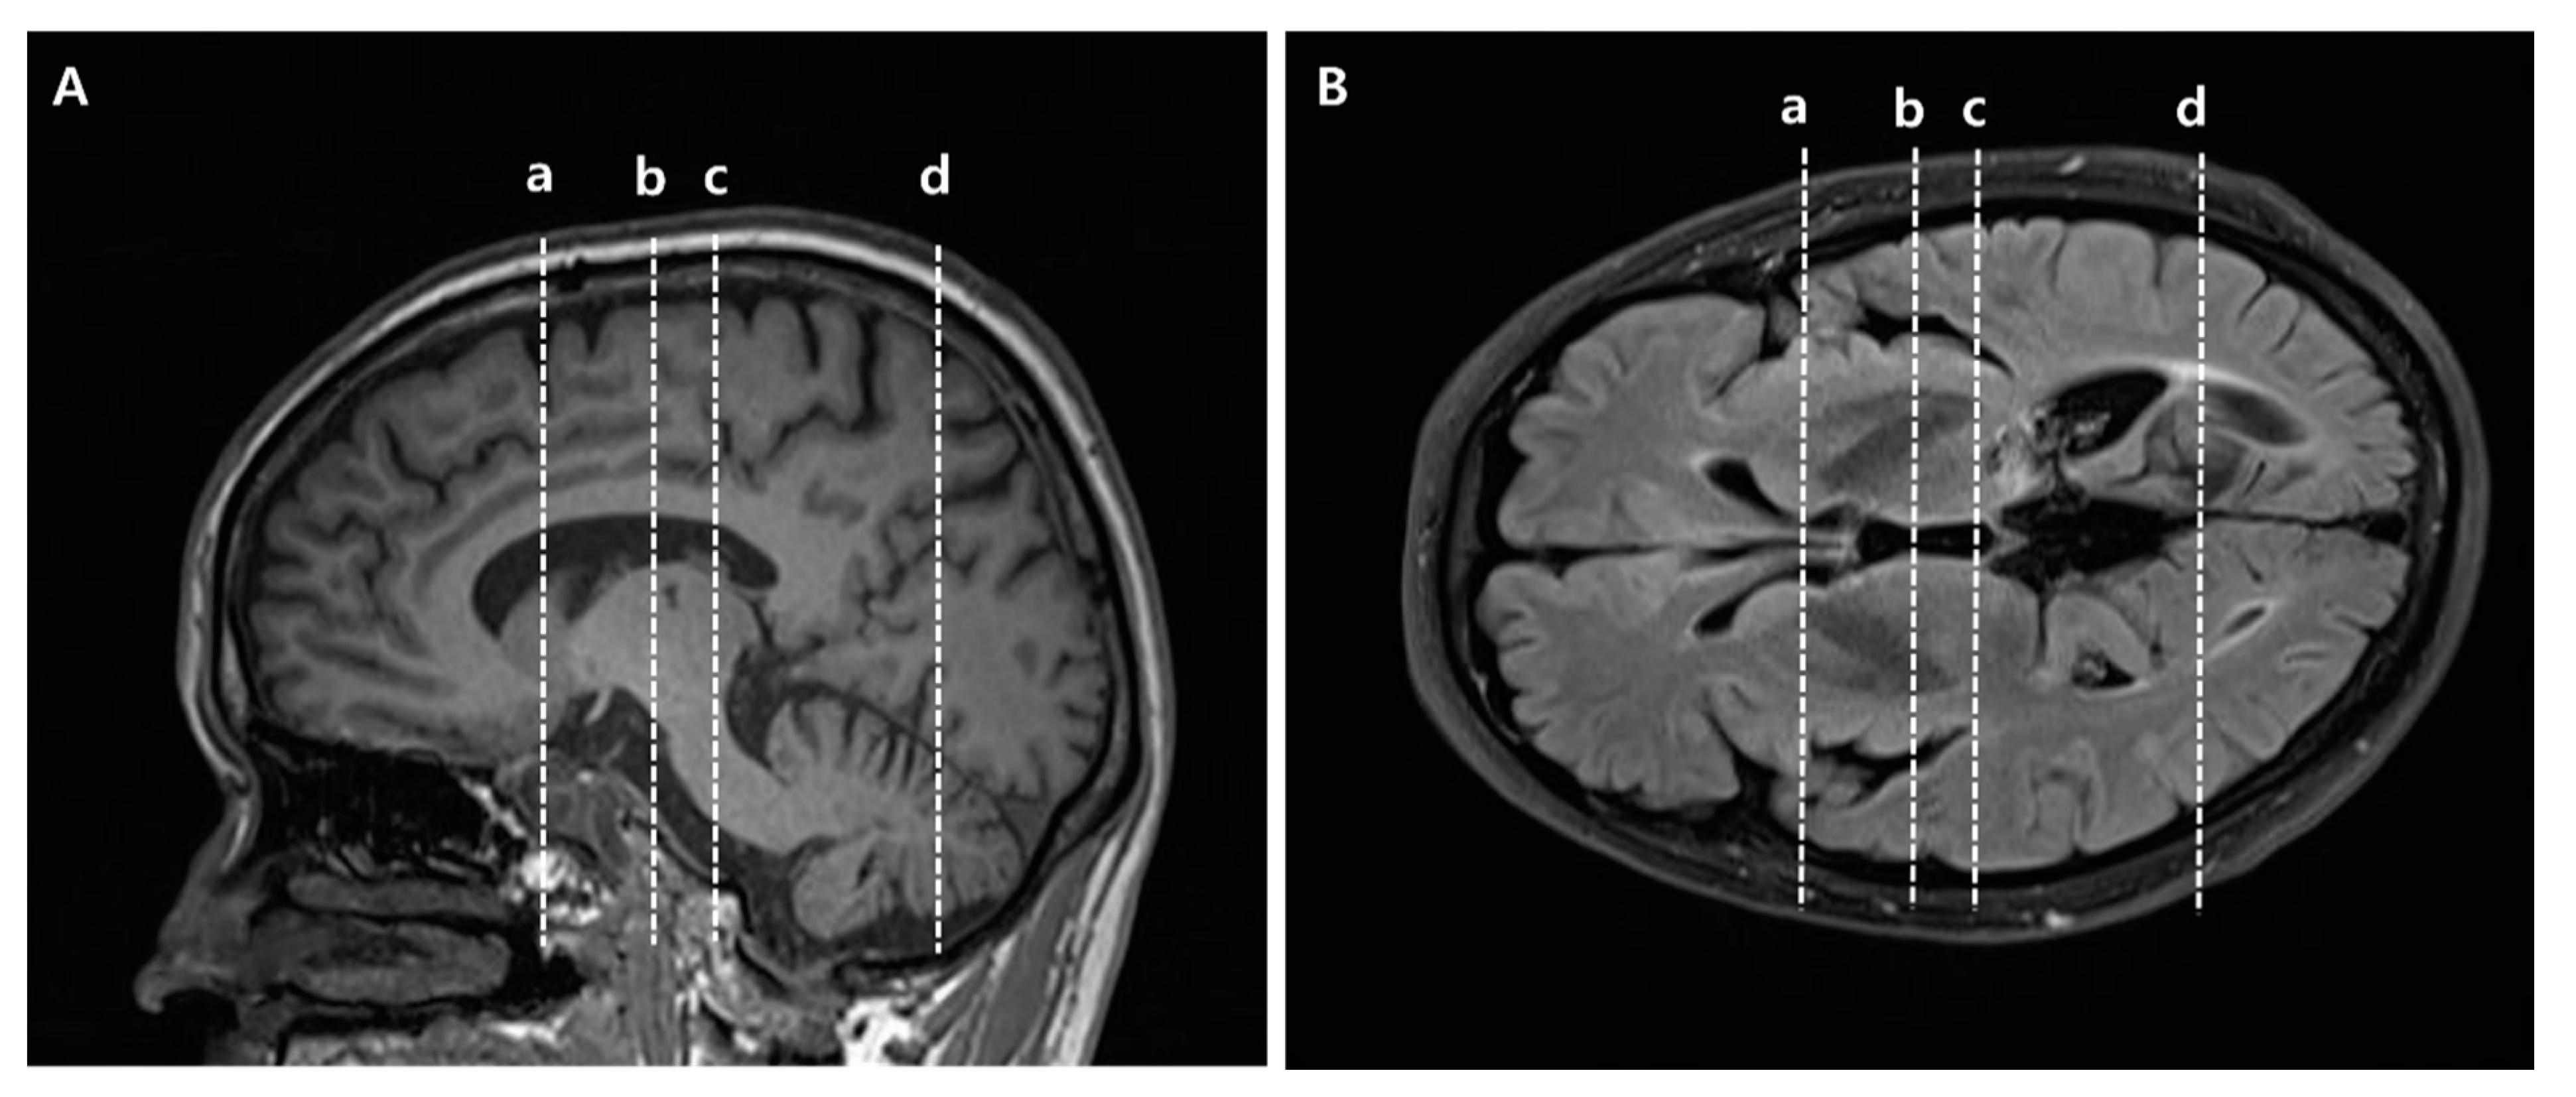

2.2. Diffusion Tensor Imaging Acquisition and Image Processing

2.3. Diffusion Tensor Tractography